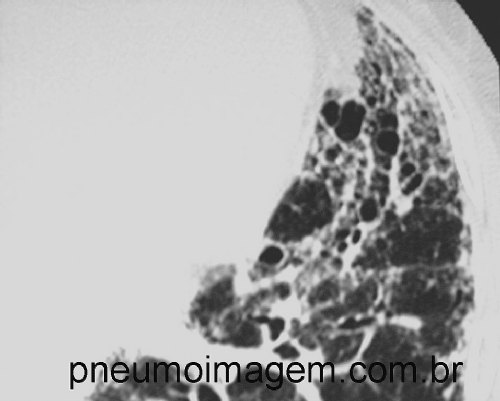

1- PADRÃO UIP/FPI

• Distribuição à TCAR: predominância basal (ocasionalmente difusa) e subpleural, frequentemente hereogênea.

• Alterações tomográficas: faveolamento; padrão reticular com bronquiectasias/bronquiolectasias de tração. Ausência de alterações não-UIP.